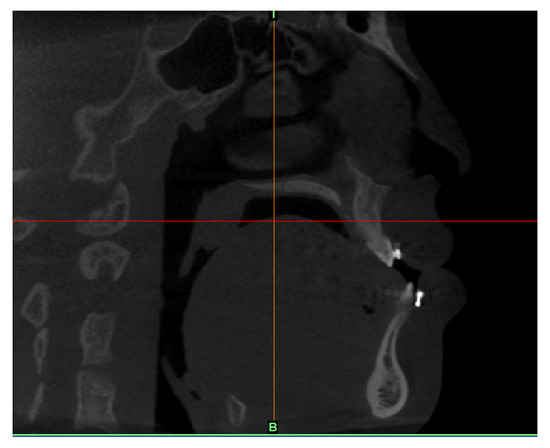

2.1. Airways Imaging Technique